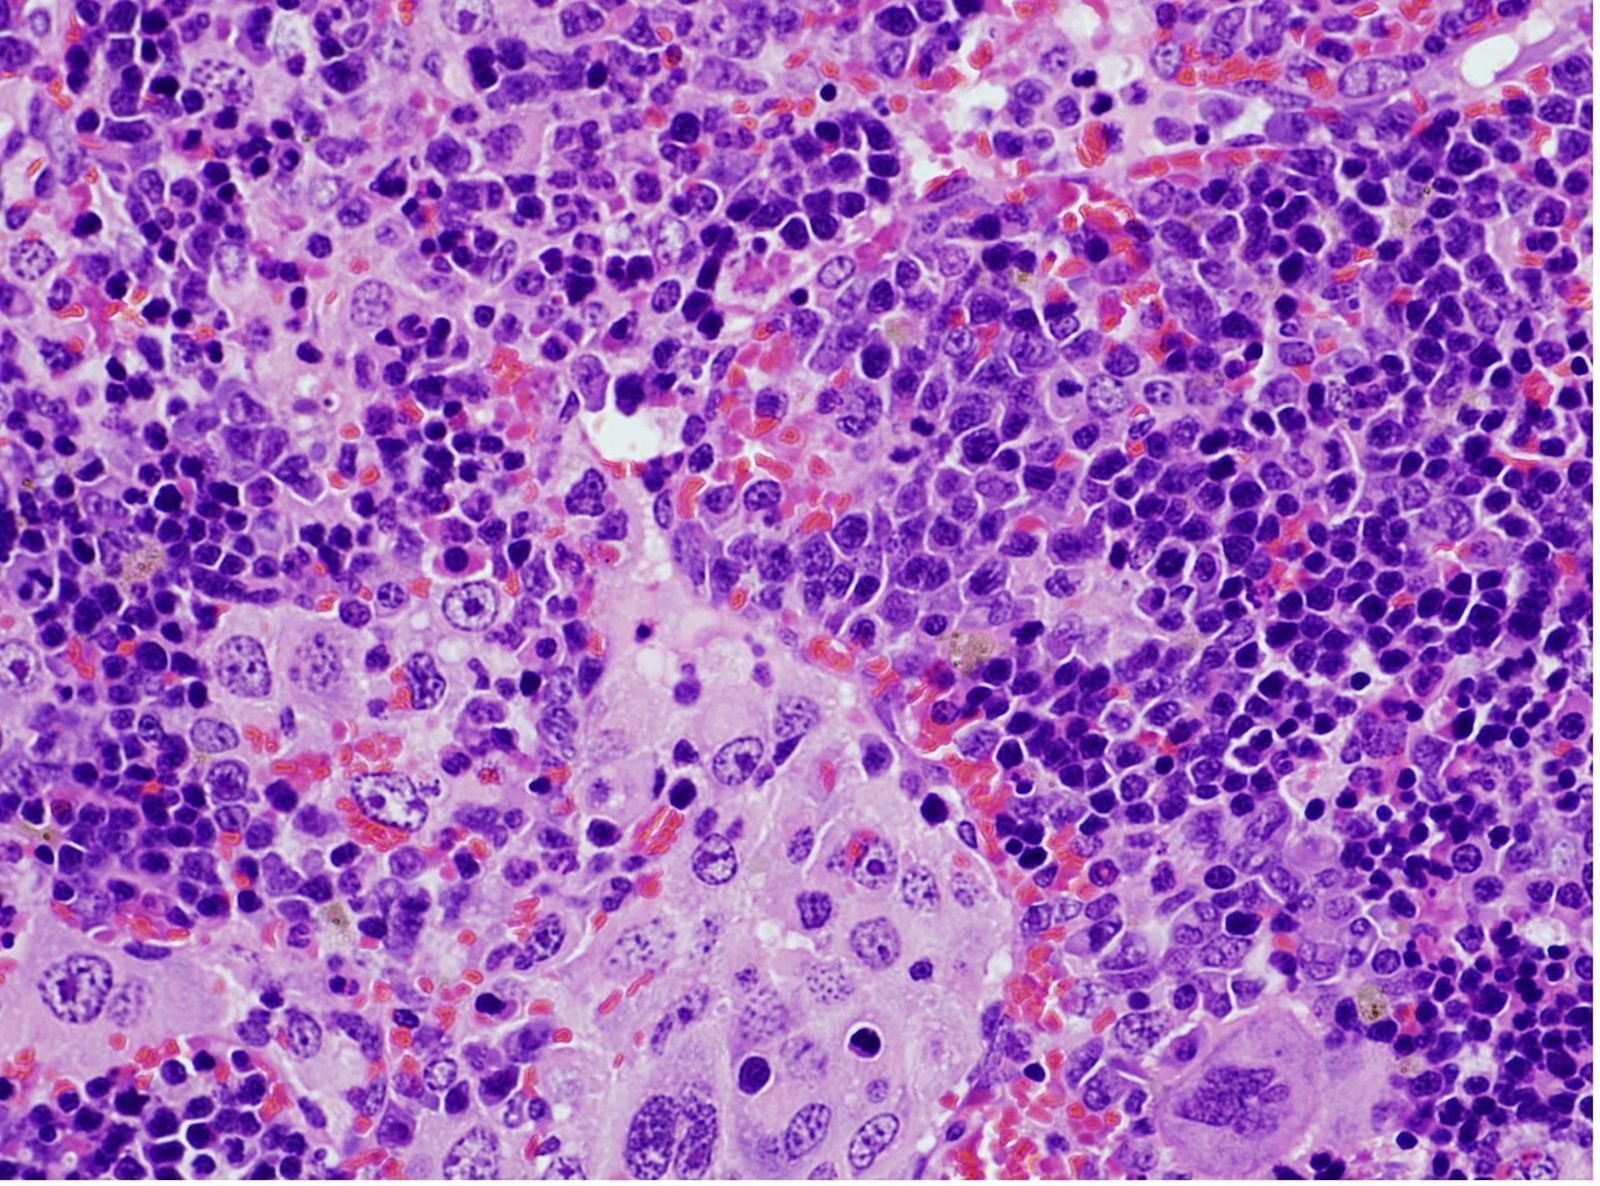

Imagen de microscopía de un bazo que presenta un linfoma desarrollado | EUROPA PRESS